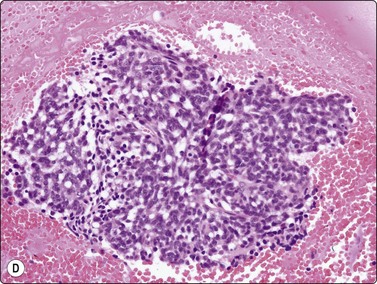

The most common sarcomas of this site include malignant fibrous histiocytoma and liposarcoma.131,132 Synovial sarcoma is well described.133 We have seen a single case of monophasic synovial sarcoma of mediastinum diagnosed on transoesophageal EUS FNB by the demonstration of SYT-SSX fusion transcripts by FISH on cell blocks, indicating X:18 translocation (all material shown here is courtesy of Dr. Anita Soma, PathWest QE II AP). (Fig. 9.10) The patient was a 45-year-old male with an 11-cm mass adjacent to the lower oesophagus, displacing the heart. Smears showed a rather bland spindle cell population but with mitotic activity. The cell block immunohistochemistry was negative for cytokeratins, CD117 and smooth muscle markers, making leiomyosarcoma and GIST unlikely. The tumor did show positive staining for CD99, BCL2 and CD34, raising the possibility of solitary fibrous tumor or synovial sarcoma. An SYT-SSX1 fusion transcript was detected by reverse transcriptase PCR, reinforcing the FISH cytogenetics. No other diagnostic procedures were undertaken (Fig 9.10).

Fig. 9.10 Synovial sarcoma

(A) Large infiltrative mass posterior to heart (Thoracic CT); (B) Loose fascicle of spindle cells including small blood vessels. Background of bare tumor nuclei (H&E, LP); (C) Loose cluster of bland spindle cells but with mitotic activity (H&E, HP); (D) Cell block, small spindle tumor cells with non-specific features (H&E, HP);(E) FISH on cell block, breakapart probe for SYT showing positive disruption of red-green-yellow components (FISH, HP); (F) FISH on cell block, fusion probe for SSX2 (green) and SYT (red) probes showing positive fusion of green and red components. (FISH, HP); (G) FISH on cell block, fusion probe for SSX2 (green) and SYT (red) probes showing positive fusion of green and red components (FISH, HP).